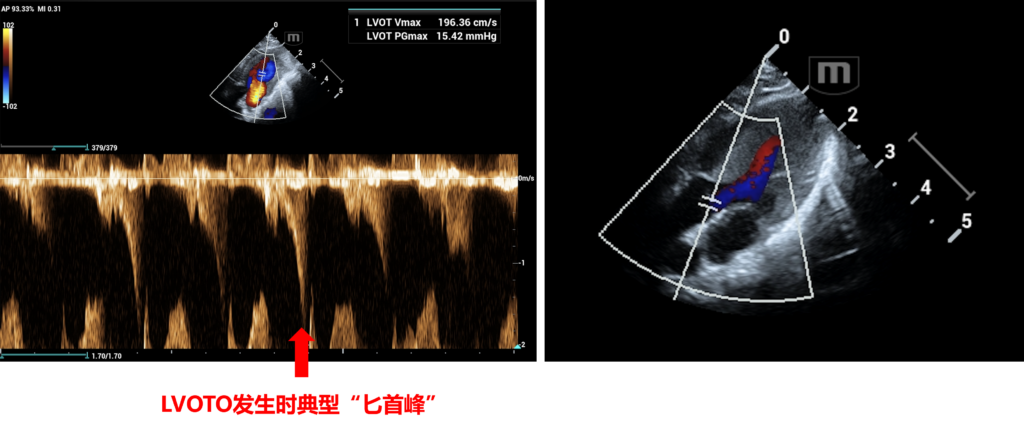

- 对标国际临床前模型标准:可稳定复现SAM症与LVOTO等典型表现

模型猫的多巴酚丁胺挑战心动超声图(Doppler Mode,数据来自以济生物)

多巴酚丁胺挑战能显著增加模型猫的LVOT PGmax,减小LVESD(数据来自以济生物)